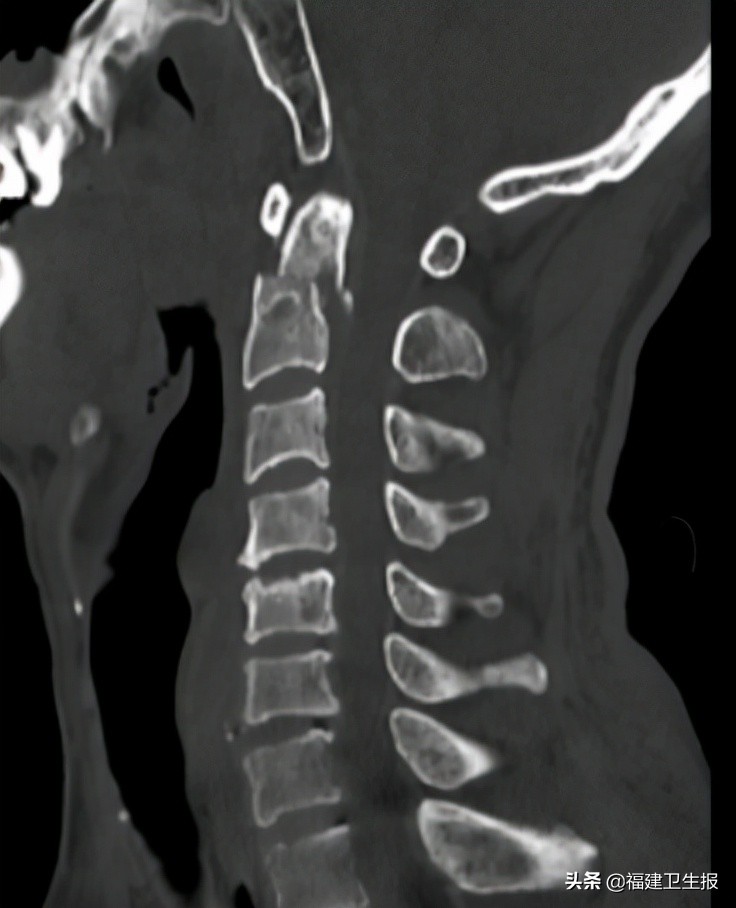

入院后,福建医科大学附属第一医院下派脊柱外科专家朱希田副主任医师接诊。进一步明确患者为高位枢椎齿状突骨折、寰椎后脱位并多节段颈脊髓损伤、多节颈椎椎体压缩性骨折并多节段颈椎间盘突出压迫颈脊髓,情况危急。

▲CT